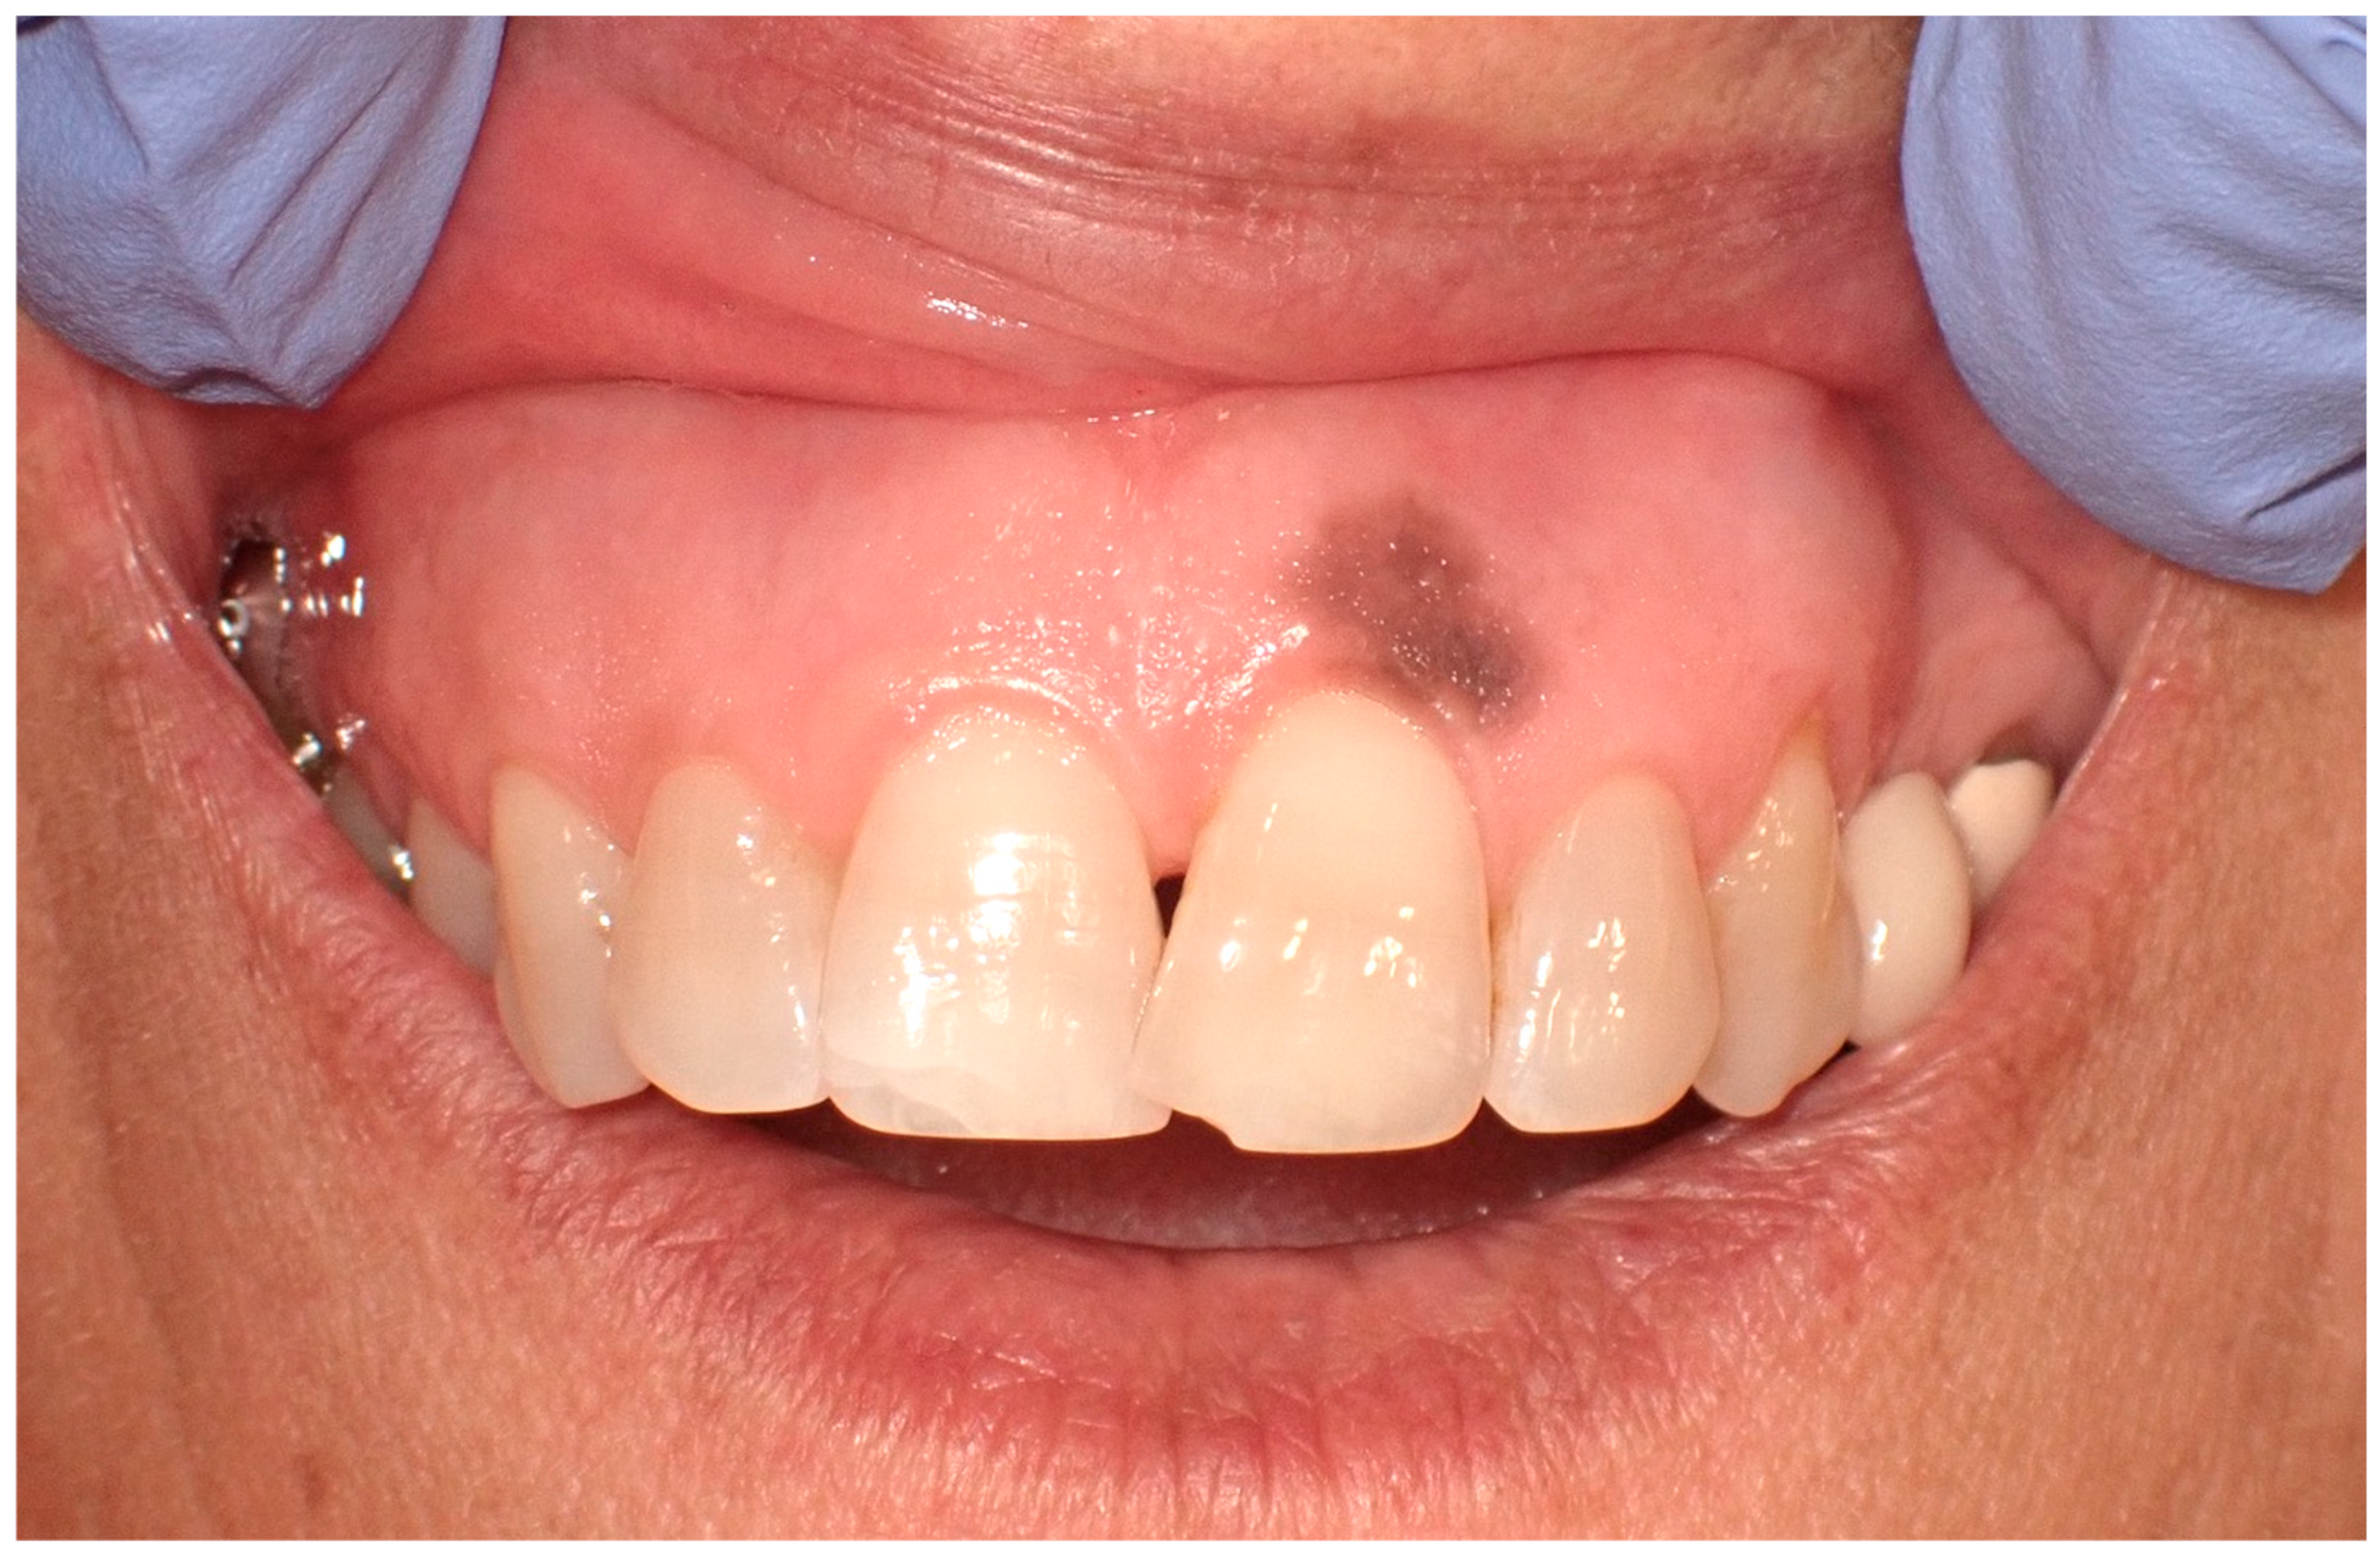

The etiology of oral melanoma remains largely unclear: unlike the more common cutaneous melanomas, which are primarily caused by the sun’s ultraviolet (UV) rays in 86% of cases, some researchers suggest that tobacco use and chronic irritation from malocclusion may play a role in its development. [35,36]. In approximately 30% of cases, the onset of the disease is preceded by a benign pigmented lesion [37,38], though it typically develops de novo on seemingly normal oral mucosa. The initial signs and symptoms often include a lesion that is soft to palpation, usually pigmented, initially asymptomatic, with irregular borders and a color spectrum ranging from dark brown to bluish-black, occasionally presenting variations of gray, purple, and red due to ulcerations, or depigmentation (Figure 5) [39,40]. The primary sites of affliction include the mucosa of the hard palate, followed by the maxillary gingiva and alveolar mucosa [29,41].

Figure 5.

Oral malignant melanoma, in the hard palatal mucosa on a 67-year-old female patient. Patient refers to these lesions as being present for 3 months. (archive S.A., patient signed the consent for clinical pictures).